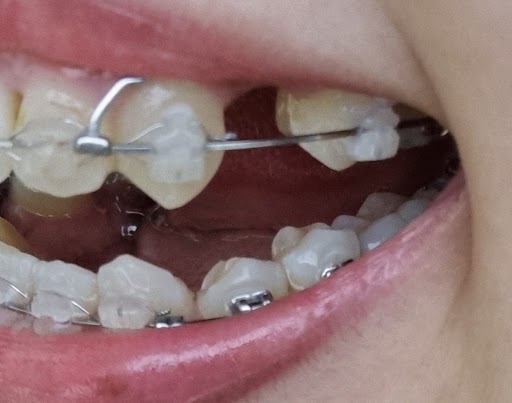

2022/10/11

2022/11/07 같은 부분의 한달 사이 변화입니다.

각도에 따라 치아의 벌어진 정도가 달라 보여서

어느정도 변화가 있는지는 잘 모르겠어요.

제 눈에는 거의 그대로로 보이는데

원장님은 0.5cm 정도 줄어들었다고 합니다.

2022/11/07 오른쪽 부분도 마찬가지로 저번달과 비교해 봤을 때

뚜렷한 변화는 모르겠어요.